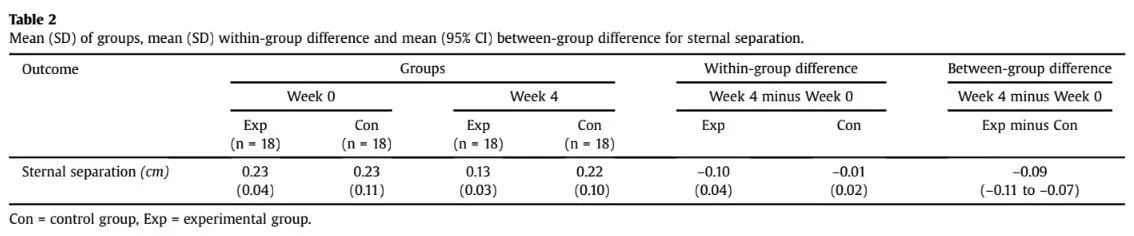

第 4 周时,实验组胸骨分离的主要结果为 0.13 厘米,对照组为 0.22 厘米。 这就产生了组间-0.09 厘米(95% CI 0.07 至 0.11)的差异,干预组更倾向于在截骨术后进行躯干稳定运动。

干预组在胸骨切开术后进行的躯干稳定练习在改善胸骨分离方面效果更好。 胸骨分离度的这一差异具有统计学意义,但置信区间非常窄,因此非常精确。 不过,改善的幅度很小: 1 毫米 然而,由于基线时仅发现 2.3 毫米的间距,这 1 毫米的改进意味着约 43% 的改进,而对照组仅有 0.1 毫米的改进(5% 的改进)。